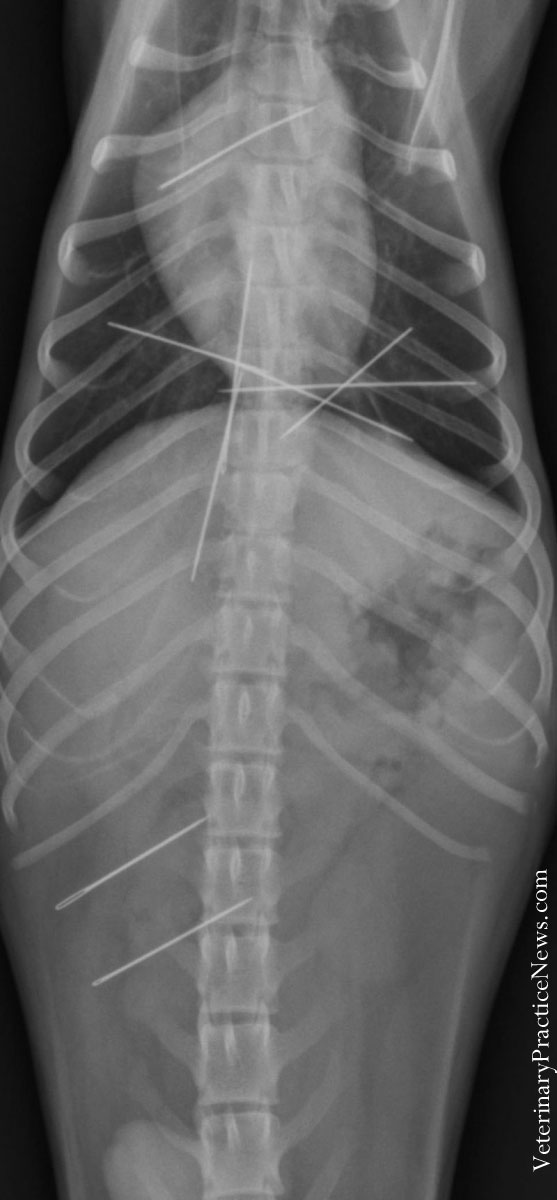

2014 X-Ray Contest WinnersAnimals will eat just about anything. The proof is in the radiographs. August 27, 2014 By Veterinary Practice News EditorsThe 2015 "They Ate What?!" Radiograph Contest Now Accepting Entries! Animal hospitals in Texas, Florida and Oregon won Veterinary Practice News’ ninth annual radiograph contest, “They Ate WHAT?” Pet insurer Trupanion of Seattle, Wash., sponsored the contest and will provide cash awards to support the uncompensated care these hospitals provide pets. The first-place winner, Paws & Claws Animal Hospital of Plano, Texas, received $1,500, Gulf Breeze Animal Hospital in Gulf Breeze, Fla., won the $1,000 second prize, and DoveLewis Animal Hospital in Portland, Ore., will receive the $500 third prize. The Veterinary Practice News editorial team and several advisory board members judged the entries. The Winners First Place: Kermit the Frog Shawn Messonnier, DVM Paws & Claws Animal Hospital Plano, Texas Kermit had the munchies. His owner noticed the exotic frog eating the rock substrate in his cage, and radiographs confirmed the owner’s observation. More than 30 small ornamental rocks were removed in surgery and the frog recovered without complications. The owner wisely decided to remove the remaining rocks from the frog’s habitat. Second Place: A Shish Kabob Skewer Goes Missing Tim Gossman, DVM Gulf Breeze Animal Hospital Gulf Breeze, Fla. Marley, a neutered male German shorthaired pointer, has always found trouble to get into. I quit encouraging his owner that he would grow out of it when he recently turned 6. Marley’s owner presented him, saying that she thought he’d eaten a shish kabob skewer. She had prepared two skewers with meat and vegetables for the grill and left them on the kitchen counter for “just a moment.” When she returned, the kabobs and Marley were gone. Finding him under the bed, the owner recovered one of the skewers, but not the other. Not thinking it was possible that he’d swallowed the skewer, I decided to radiograph Marley to appease the owner. Well, there it was, within the stomach. The exploratory and gastrotomy were uneventful. Marley was soon out the door and on to his next adventure. Third Place: Great Dane Eats 43 1/2 Socks DoveLewis Emergency Animal Hospital Portland, Ore. A 3-year-old male Great Dane was observed repeatedly vomiting and retching all day. Abdominal radiographs revealed a severely distended stomach and a large quantity of foreign material. During exploratory surgery performed by a DoveLewis veterinarian, 43½ socks were removed. The patient was discharged home one day after surgery. The Great Dane is still doing well, according to the family, and the Internet has fallen in love with his story. Honorable Mentions The Curious Case of Dragon Andrew Rambo, DVM Gladstone Animal Clinic Gladstone, Mo. A woman brought a bearded dragon named Dragon into our clinic for acute anorexia. Her young granddaughter was distraught that their beloved lizard was turning its scaly nose up at food. After a bit of persuading for an X-ray (“After all, it’s not a dog … but our granddaughter does love it so.”) an unusual opacity—remarkably shaped like a banana!—was observed in its digestive tract. The granddaughter’s comment: “That’s where Barbie’s banana went!” Apparently, Dragon had been known to lounge in Barbie’s Dream House when being played with by the granddaughter. veterinarypraticenews.com Dragon, a bearded dragon, came into the Gladstone Animal Clinic when he refused to eat. veterinarypraticenews.com According to Andrew Rambo, DVM, upon seeing the banana, Dragon's owner exclaimed, "So that's where Barbie's banana went!" Hook, Line & Sinker Josh Brown, DVM The Animal Clinic PSC Lawrenceburg, Ky. On a Saturday night, the owners brought in Elvis, a 7-week-old, 6.5-pound male mixed-breed puppy. They had been catfishing and baiting their hooks with chicken livers, which Elvis apparently found too tempting to ignore. He gulped down a liver—hook, line and all. He presented to our clinic after hours. A gastrotomy was performed to remove the hook, which had perforated the stomach. Fortunately, a timely surgery and antibiotics provided Elvis with a full recovery. Teresa Smith, DVM Heron Creek Animal Hospital North Port, Fla. A 5-month-old male kitten presented for acute anorexia and repeated vomiting. The owner recognized the toy alien figure on the X-ray. In surgery, it was found lodged in the proximal duodenum. Due to the “thumbs” of the toy, it could not be moved retrograde and the intestine had to be incised to facilitate removal. The cat recovered uneventfully and did well post-op. Is That a Lightbulb? Christy McCratic, DVM Golf Rose Animal Hospital Cody, a 10-month-old, 58-pound golden retriever, had been vomiting for two days before the owner approved radiographs. The light bulb passed intact after a day on intravenous fluids. Rubber Ducky, You're the One Mary Green, DVM Animal Emergency of Pasco Port Richey, Fla. A client with a dog named Woof called, saying her dog had eaten a rubber duck. Her 3-year-old son had lost his rubber duckie, so Mom, unable to find it after a month, bought him a new one. Watching her son in the tub, she saw Woof come in, nose around in the water and gulp down the duckie. Radiographs found five rubber duckies. Every time a duck went missing, Mom would buy a new one. We surgically removed the flock along with a toy truck tire and a piece of another toy, and Woof did very well. Pins & Needles (But Mostly Needles) Diane Craig, DVM, Dipl. ACVS Veterinary Surgical Specialists Inc Tustin, Calif. Yoda, a 9-pound Chihuahua, presented for shoulder lameness. The radiographs showed nine needles. Surgical removal of nine sewing needles from all over the body required a ventral abdominal exploratory and a ventral sternotomy. Presumably he ate a package of needles and digested the paper, and the needles migrated through his body. The lameness was caused by the one that was poking into his brachial area. He is doing well. For Turtles Only Christina Fenton, DVM Glenwood Falls Animal Hospital Cypress, Texas A 12-year-old male neutered Welsh Corgi ate approximately 2 cups of pea gravel. The owners had cleaned out the turtle tank and dumped the gravel in the flower bed. They then cleaned the barbecue grill and dumped the grease over the gravel. He recovered from surgery without incident. Dog Plus Change Holly Meuser, DVM Acequia Animal Hospital Albuquerque, N.M. Two-year-old pug Stella presented for vomiting 40 times overnight. During an abdominal exploratory, one quarter and 104 pennies were removed from the stomach. This patient recovered fine, but the $1.29 did not go toward her bill. Is That a Knife in Your Stomach? Kacie DuRocher, veterinary assistant Capitol Illini Veterinary Services Chatham, Ill. Lucy the Labrador came to us while staying with grandpa. She had found a closed pocketknife on the coffee table and swallowed it. We fed her a small meal and administered Apomorphine. A quick vomiting episode produced the 9.2 by 2.3 cm pocket knife. Hacky Sack Wendy J. Kollar, DVM VeterinaryPracticeNews.com D'Jango, the puppy who ate a hacky sack, wasn't feeling well when he was brought into the Akron Veterinary Referral and Emergency Center. Akron Veterinary Referral and Emergency Center Akron, Ohio Owner returned home to find D’Jango, a 15-week-old male intact golden retriever, playing with a Hacky Sack. Her son said another Hacky Sack was missing. Radiographs showed the puppy had eaten it and it appeared to be whole. Client elected for emesis. Apomorphine was administered conjunctively. After a second dose D’Jango vomited food and an intact Hacky Sack. Know Your Size Dr. Aaron W. Wilfert DVM Jackson County Veterinary Clinic PLLC Edna, Texas What is more embarrassing than your vet and his entire staff knowing your bra size? Norris, a 2-month-old rat terrier, presented with vomiting and stomach pain. Radiographs found a small metal clip in the stomach. The owner was asked to view the radiographs to identify the object, with the (male) veterinarian present. We don’t know who was more embarrassed, the owner or the veterinarian, when she determined that Norris had eaten her bra. Approximately 14 inches of bra and bra strap was surgically removed from the stomach and small intestine. Norris is thriving, but he is no longer allowed to enter the family laundry room. "They Ate What?! Contest": A Tradition Since 2006 Veterinary Practice News editor Marilyn Iturri created the “They Ate WHAT?!” contest in 2006 to showcase the humorous situations veterinarians and pet owners can face as well as the clinical advances available through digital radiography. The competition was a hit with readers from the start. Some trends have been apparent from the first year. “This year’s entries featured some of our old standards, such as cats eating hair ties and hair bands, threaded sewing needles and other shiny objects,” Iturri said. “Dogs often seem to eat golf balls, small rubber balls, rubber ducks and clothing items, plus a variety of metal objects not meant for consumption.” What stood out this year was what the animals had eaten and how much, according to Iturri. “One dog had swallowed five duckies and one of our top three winners ate 43.5 socks,” she said. “That broke our socks-eaten record. And a pug ate a package of sewing needles, which previously we saw only cats do. Unlike previous years, the items eaten by pets weren’t as expensive as previous years. “One thing we didn’t see this year was radiographs of expensive diamond rings in dogs,” Iturri said. “One year, two were entered, both reportedly worth $15,000. Another year, a cockatiel had swallowed an engagement ring.” Despite the light-hearted nature of the contest, Iturri said, the message to pet owners is serious. “Don’t trust your pet not to eat something she shouldn’t,” she said. “And if you think she ingested a foreign body, get her to your veterinarian right away. The longer you wait, the more damage is possible and it can be harder to retrieve the item.” Trupanion of Seattle sponsored this year’s contest. T.J. Houk, the pet insurer’s director of business intelligence, says its data suggest that as a foreign object passes through the animal’s body, costs to treat it increase – with more pain for the pet and possibly a worse outcome. Houk said the average cost of a claim for an object caught in the esophagus is about $800, which increases to a little more than $1,000 when the object moves into the stomach and to more than $1,700 when it reaches the intestines. If it remains untreated, Houk said, the intestine can rupture and pets can get septic abdomen and peritonitis, which can cost $5,000 or more. While the contest is over, Iturri said the call for new X-rays begins April 2015. The contest will be announced both on VeterinaryPracticeNew.com and the Veterinary Practice News magazine. See More X-Rays: 2013 X-Ray Contest Winners 2012 X-Ray Contest Winners More Crazy X-Rays Follow Veteriary Practice News on Twitter at @vetpetnews Originally published in the September 2014 issue of Veterinary Practice News